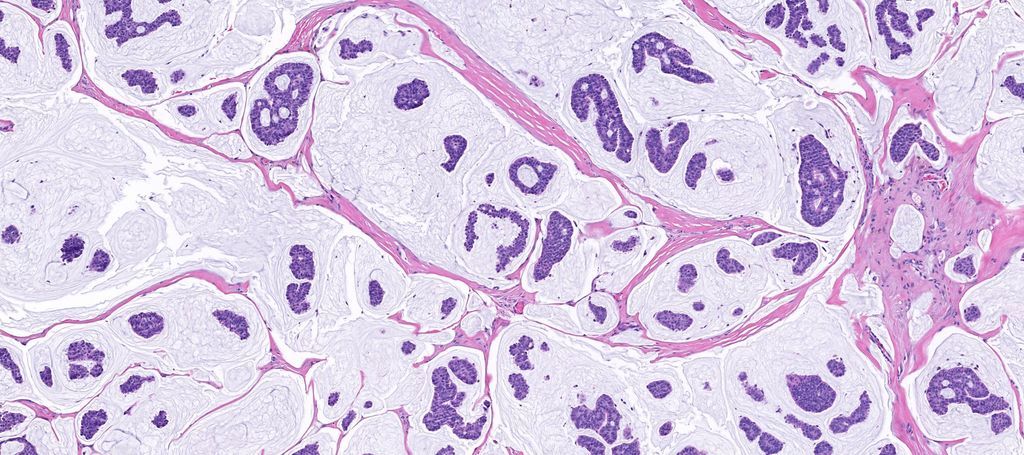

65 year old man posterior auricular neck deep dermal nodule. easy peezy?#dermpath #PathTwitter #dermatology Etan Marks, DO @ArjunRamaiya1 Lorand Kis Olaleke Folaranmi Tristan Rutland MBBS FRCPA IFCAP Trish Stratus Marcelasaeblima. Allison Osmond MD MSc FRCPC Ahmed Alomari, MD Gonzalo De Toro